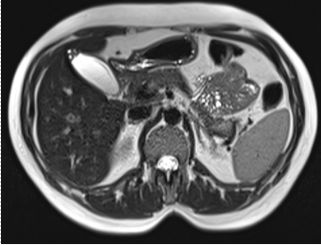

Safra Kesesi Adenomiyomatozisi

Adenomiyomatozis, kese duvarında iyi huylu bir kalınlaşma olup fokal (bölgesel) veya difüz (yaygın) duvar kalınlaşması ile karakterizedir. Bu durumda kese duvarındaki mukoza katmanı, kas tabakasının içine doğru fıtıklaşarak "Rokitansky-Aschoff sinüsleri" adı verilen küçük cepler oluşturur. Genellikle zararsız olarak kabul edilse de, safra çamuru birikimine neden olabileceği için takibi önerilir.